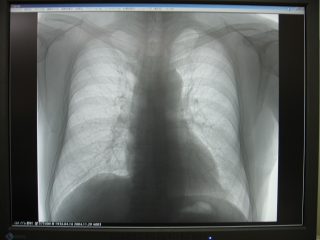

1)画像が美しく鮮明である

デジタル化したことにより、今までは不可能だった軟部組織から骨までを一枚のレントゲンで見ることができます。自動感度調整機能により、常に均一で安定した濃度の高画質なX線画像が得られるので診断精度が向上します。

6)モニター表示ができる

X線撮影後、約2分で診察室に置いたモニターに撮影したX線画像が表示されます。これを等倍表示にしておくと、モニターには通常のアナログX線フィルムと同じ大きさで表示されます。EIZO 21.3インチの液晶モニターに表示された画像は、アナログX線フィルよりも鮮明で、これだけ鮮明なら臨床的にはフィルムに勝るとも劣らないと思います。その画像が従来のフィルム現像よりもかなり早く表示されるのだから非常に有用です。(写真5参照)